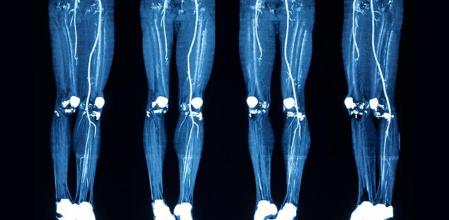

La enfermedad de Buerger se puede confirmar mediante análisis de sangre que descarten otras enfermedades con síntomas parecidos; una ‘prueba o test de Allen’ para confirmar el flujo sanguíneo en la sangre que llega a las manos; y una angiografía para conocer el estado de las arterias.